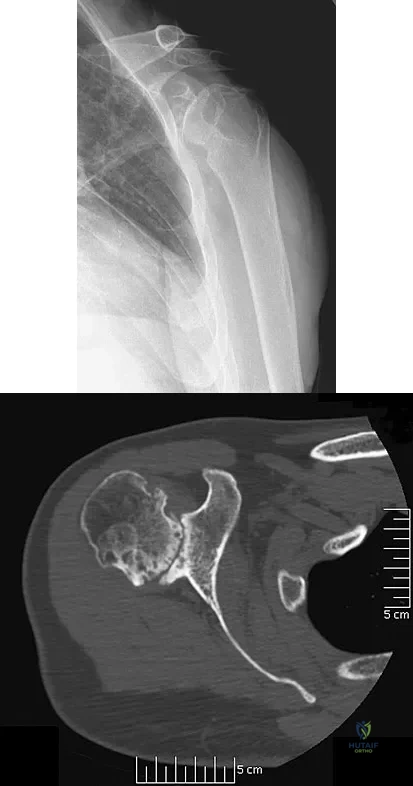

A 16-year-old girl has had hip pain for 1 year. Approximately 2 months ago she noted the development of a hard mass in the right buttock that has steadily increased in size. She now reports severe pain in the right buttock, with radiation down the leg and numbness involving the right foot and toes. A radiograph is shown in Figure 70a and an axial postcontrast T1-weighted MRI scan is shown in Figure 70b. A biopsy specimen is shown in Figure 70c. The chest CT shows multiple lung metastases. Treatment of this lesion should consist of

Explanation